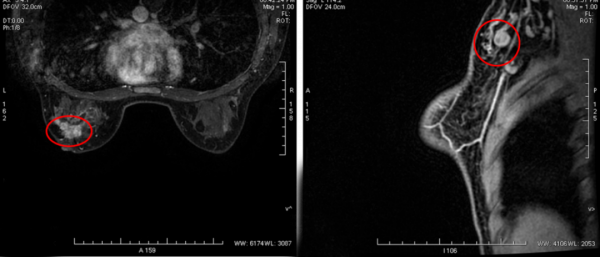

乳腺磁共振:左乳外象限可見不規則性腫塊,呈等T1等T2訊號,範圍約3.1*4.2*4.4cm,增強後呈明顯強化,與鄰近乳頭關係密切,其周圍可見多發強化結節灶,左側乳頭未見明顯內陷,病灶距鄰近胸大肌2.2cm,距離乳腺面板約1.4cm,距離乳頭約0.5cm。左側腋窩可見多發腫大淋巴結,較大者約1.5*1.0cm(圖3)。

2. 乳腺磁共振(6個週期新輔助治療後):與治療前(圖3)相比,原左乳外上象限結節灶大小約0.5*0.9*0.5cm,增強後呈明顯強化,病灶距鄰近胸大肌4.2cm,距離乳腺面板約1.0cm,距離乳頭約1.1cm。左側腋窩未見增大淋巴結(圖5)。